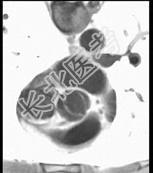

- 单项选择题下面一组图像考虑为 ( )

A、正常的肺动脉瓣

B、正常的二尖瓣

C、正常的三尖瓣

D、正常的主动脉瓣

E、变异的主动脉瓣(两个瓣膜)